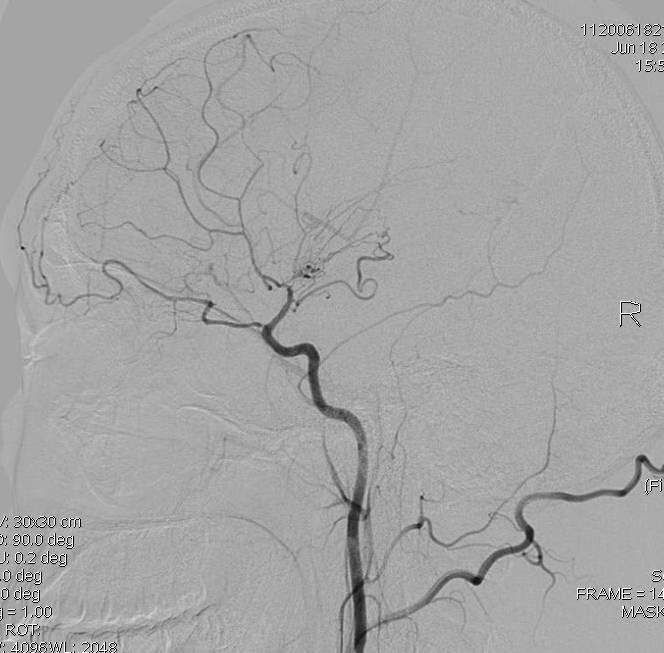

DSA显示右侧大脑中动脉分支减少:

DSA显示右侧颈内动脉末端闭塞: